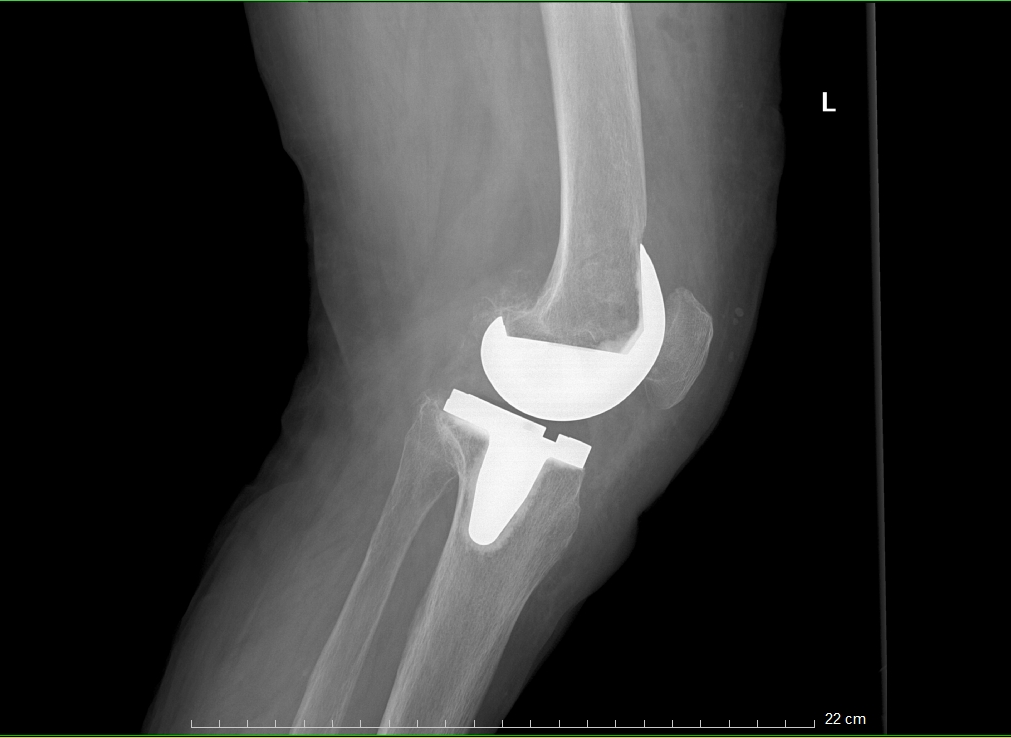

患者术后X光扫描

这个过程可以类比为镶牙,即切除受损部分并替换为金属材料。同理,在膝关节置换术中,医生会移除严重磨损的关节表面软骨及部分软骨下骨,在原位安装与原始膝关节表面形状类似的金属组件(即假体),使用骨水泥将假体与患者自身的股骨和胫骨固定在一起,使之恢复膝关节的正常功能。

患者术前VS术后对比